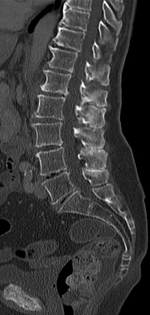

Baastrup's sign, or kissing spine, is an orthopedic and radiographic disorder that often occurs in elderly humans. It is characterized by enlargement of the posterior spinous projections of the lumbar spine, with normal intervertebral disc height and neuroforamina. The reason it is referred to as kissing spine is because the posterior spinous processes 'kiss' and touch one another as the individual goes into lumbar extension, for example when flat on their stomach.[1][2][3] The condition has been seen in humans, canines, particularly with boxer breeds,[4] and certain breeds of horses.[5] This disorder is named after Christian Ingerslev Baastrup.

The salient feature of the disorder is the exuberant osteophytosis that occurs at posterior lumbar spinous processes. Osteophytes are coarse calcifications at the edges of bone that form due to repetitive stress and trauma. There is also atrophy and fatty replacement of paraspinal musculature, which can be detected by CT or MRI.[6]